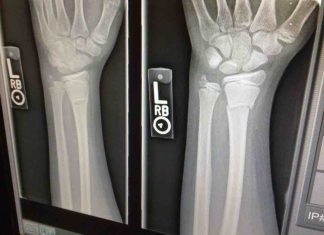

Study: Even fractures in arm, wrist increase risk for future breaks...

Current guidelines for managing osteoporosis specifically call out hip or spine fractures for increasing the risk for subsequent bone breaks. But a new UCLA-led...